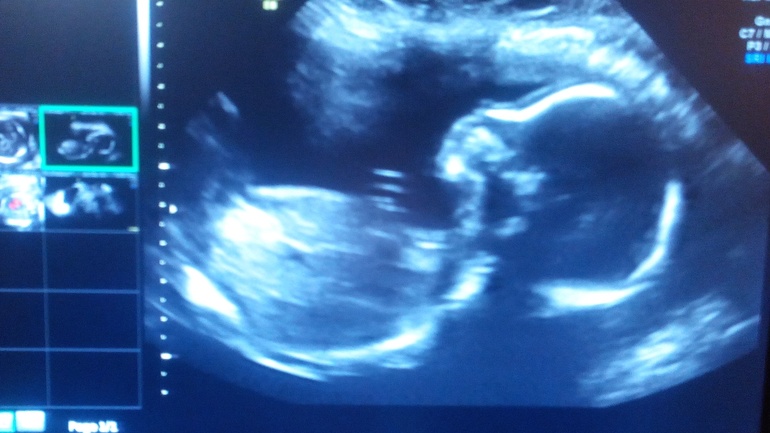

Перешли рубеж в пол срока. Сходили на скрининг. У нас все в порядке и это радует!!!!! В нашей семье будет принцесса!